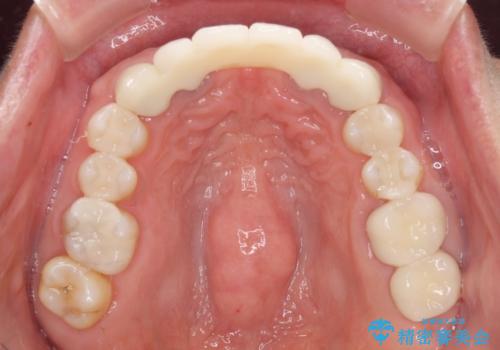

金属を使用した前歯のブリッジや奥歯の銀歯は全てオールセラミッククラウンまたはセラミックインレーとし、左下の奥歯はインプラントにより治療を行うこととしました。

遠方からの来院であったので、1回の治療時間を長めにし、できる限りの処置を集中して行うことで、来院回数を減らすことができました。

初診カウンセリングを含めて13回の通院で治療を終えることができ、患者様には大変満足していただきました。